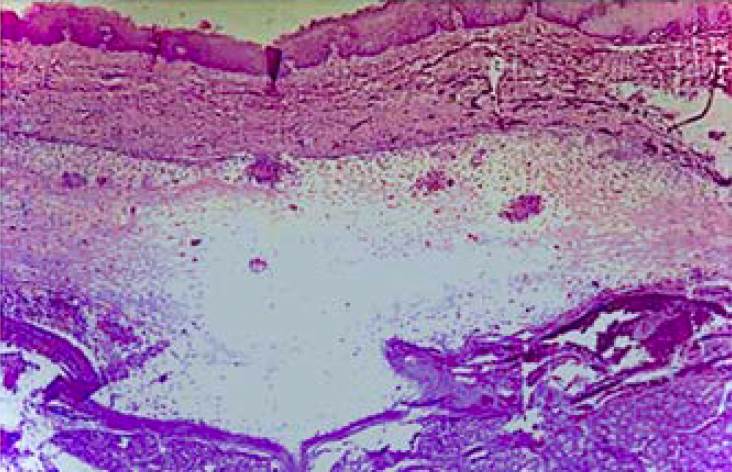

Durante el periodo evaluado (1997-2017), se recibieron y procesaron 14,186 muestras en el SAPyC del Hospital Pediátrico «Juan Pablo II», de los cuales 63 casos correspondieron a lesiones de las glándulas salivales. Cuarenta y siete tuvieron diagnóstico histopatológico de mucocele (Figuras 1 y 2), representando el 74.6% de las lesiones de glándulas salivales, siendo por lo tanto la patología más frecuente en la población estudiada (Tabla 1).

Figura 2 Características histopatológicas. Al examen microscópico se observa: mucosa revestida por epitelio escamoso no queratinizado, ligeramente aplanado y desplazado por una cavidad circunscripta localizada en tejido conectivo y submucosa, revestido por tejido de granulación, con abundante extravasación de material mucoide. 10×, H/E .